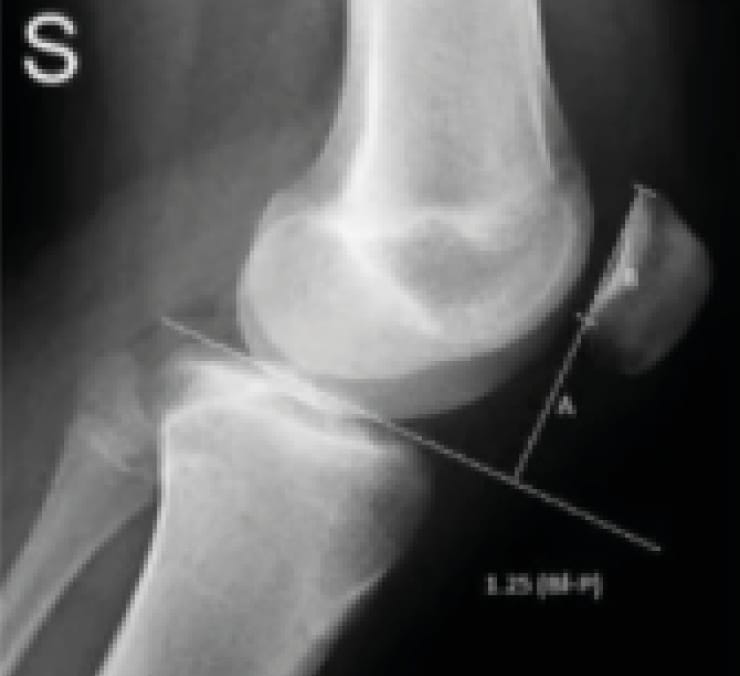

The Caton index (Figure 11), which became the Caton-Deschamps index, was considered normal for values between 0.8 and 1.2. Above 1.2, the patella is high or alta. Below 0.8, the patella is low, infera, or baja.

The first of the main factors: patella alta.

It is defined by the Caton-Deschamps index AT/AP greater than 1.2. This is an index that refers to the tibia and not the trochlea. We found patella alta in 30% of patients belonging to the objective patellar instability group.

Perhaps more importantly, up to 40% of recurrent instability cases after surgery may be related to the failure to address patella alta (C. Levigne’s thesis, 1988).